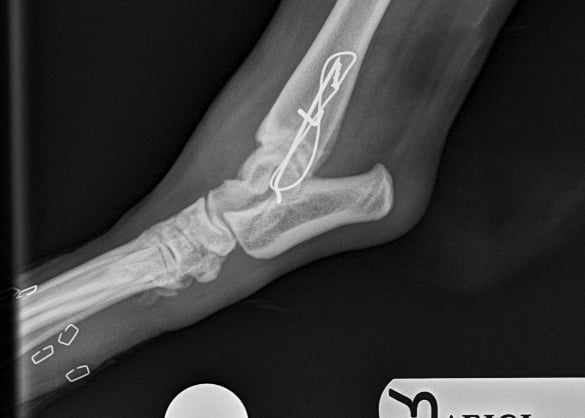

Lateral approach to the talocrural joint reveals severe oedema and bruising, 1.2mm IM pin placed in a distal to proximal fashion, 0.75mm cerclage wire used to create a figure-of-8 tension band. 1.4mm pin placed parallel to the talocrural joint from lateral to medial (Fig 3 and 4).

Buddy recovered well and in 4 weeks post op Xrays we could see that the fracture was healing well (Fig 5 and 6).

Fig. 6

Fig. 5

Fig. 4